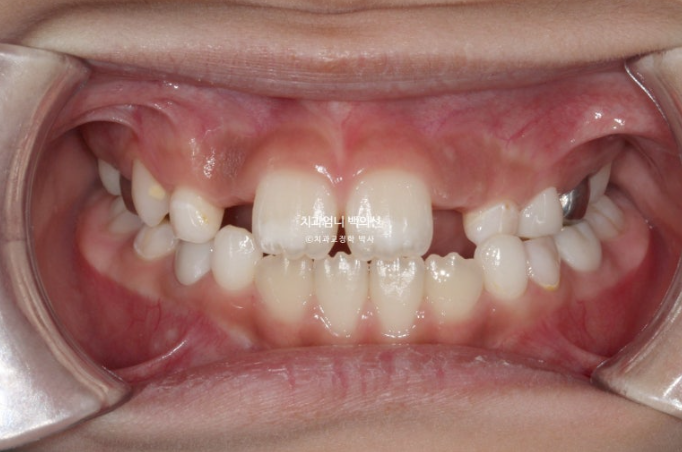

23년 12월 교정치료를 위해 내원한 만 8세 어린이 입니다.

타치과에서 반대교합, 비대칭, 공간이 부족하여 앞니가 못 나오고 있다는 이야기를 듣고 교정을 위해 내원했습니다.

중심선이 많이 어긋나 있으며 파란화살표는 위아래가 거꾸로 물리는 반대교합입니다.

노란색 아래턱의 중심, 흰색이 윗턱의 중심선입니다.

아래턱이 치아중심선 만큼 왼쪽으로 틀어진 비대칭입니다.

유치송곳니끼리 거꾸로 물리는 상태라 이 부분에 교합간섭이 있습니다.

교합간섭에 의해 턱을 한쪽으로 틀어서 물게 되는 경우가 있습니다.

이 경우 악궁확장으로 거꾸로 물리는 부분, 즉 교합간섭을 해결해주면 비대칭이 자연스럽게 좋아지기도 합니다.

윗니가 아랫니를 덮지 못하는 절단교합입니다.

측절치와 송곳니날 자리가 부족해서 악궁확장도 필요한 상황입니다.